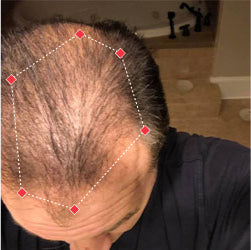

Indications for Use

The iRESTORE Hair Growth System Elite is indicated to promote hair growth in males who have Norwood-Hamilton Classifications of IIa to V and in females who have Ludwig-Savin Classifications I to II, and in both with Fitzpatrick Skin Phototypes I to IV. In other words, iRESTORE is not intended for people who are bald or have advanced hair loss.

Read more in our user manual for Indications of Use, Contraindications, Warnings, and Precautions to find out if iRESTORE is suitable for you.

Laser therapy works to reactivate thinning and dormant hairs. For completely bald areas of the scalp, there may be no way to promote hair regrowth. If you still have hair follicles, laser therapy may be beneficial to you.

Not sure? Email us to have our specialists evaluate your scalp conditions to see if iRESTORE is suitable for you.